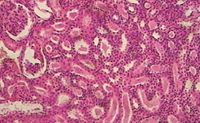

Гистологический срез почки: изучаем микроструктуру